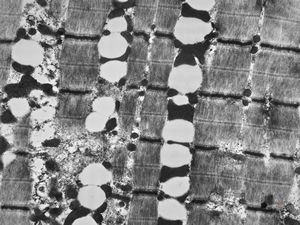

F,25y. | myopathy - atrophic and regenerating muscle cells

M,2y. | myopathy - regenerating muscle cell